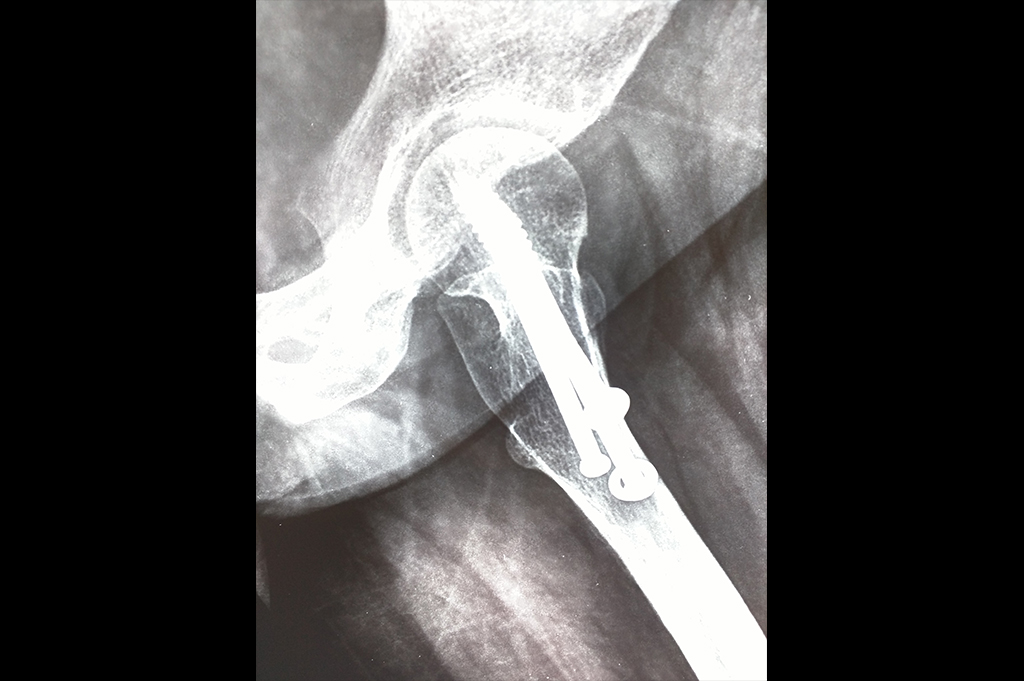

Subtrochanteric Fracture